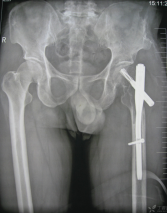

内固定

接骨板、螺钉

C:\Users\ADMINI~1\AppData\Local\Temp\ksohtml5168\wps19.png

髓内钉、克氏针

C:\Users\ADMINI~1\AppData\Local\Temp\ksohtml5168\wps20.pngC:\Users\ADMINI~1\AppData\Local\Temp\ksohtml5168\wps21.png